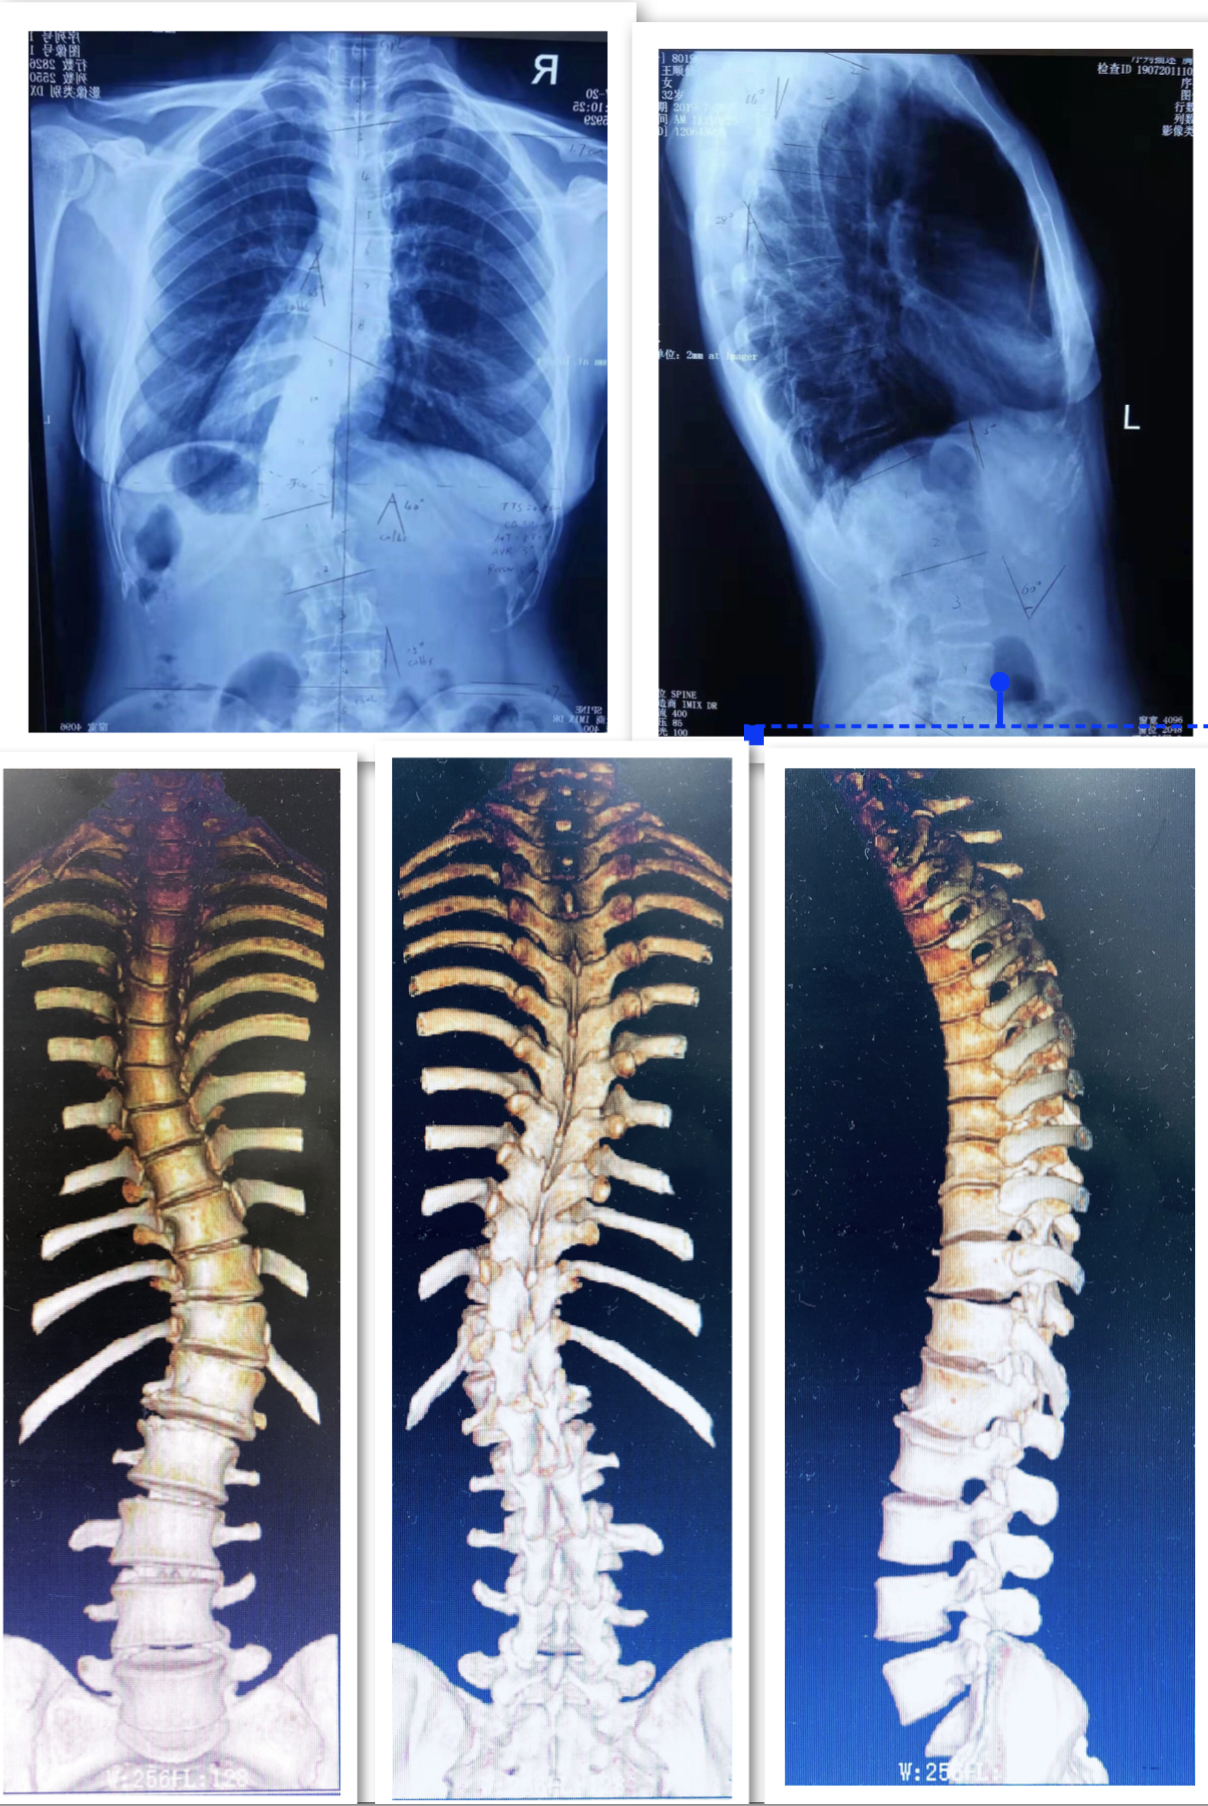

病例一:患者马某,男性,16岁,贵州省威宁县人,因“发现胸腰背部畸形3月余”入院,诊断为:脊柱侧后凸畸形并功能障碍,行经后路胸椎SPO截骨矫形钉棒系统内固定融合术。

术前DR及CT

术后DR

术前术后站立位对比